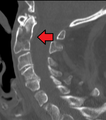

A fracture of the base of the dens as seen on CT